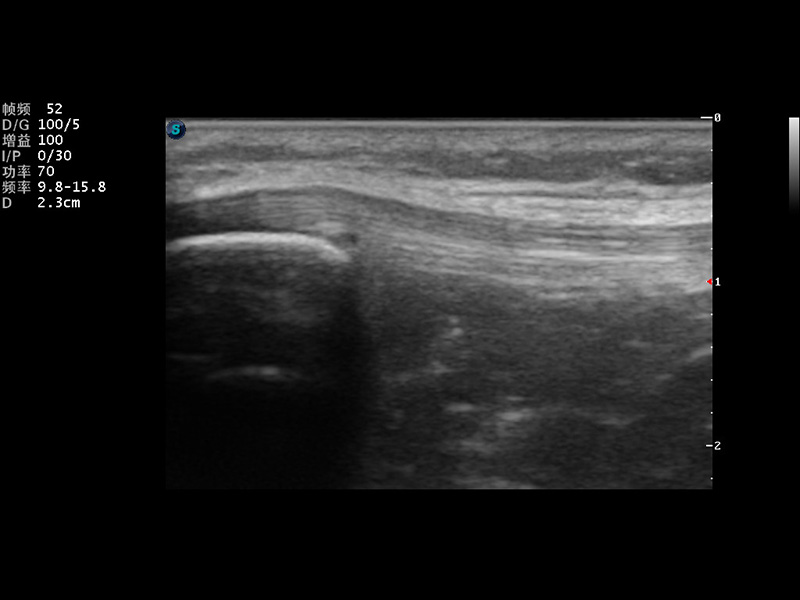

μ-Scan微米成像